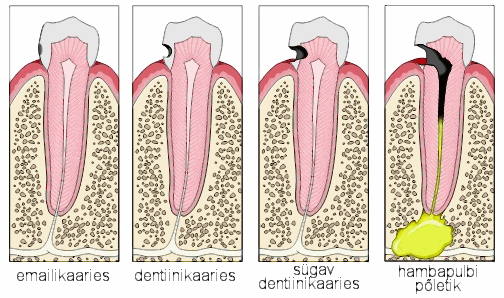

Hambakaariese 4 staadiumi

Emailikaaries on pindmine kahjustus, mille puhul karioosne defekt asub emailis. Märgatav on piimjasvalge värvusega defekt, harvem pigmenteerunud hambapind. Viimast võib leida purihammaste hambavagudes ehk fissuurides.

Dentiinikaaries on dentiinikihti osaliselt haarav defekt e. hambaauk milline ulatub emaili all hambaluusse. kuid pulbi kaitseks jääb veel küllalt kahjustamata kudet. Võrreldes emailiga on dentiin vähem kaltsifitseerunud ja sisaldab mikroskoopilisi õõnsusi (tuubuleid), mistõttu allub kergemini hapete ja mikroobide mõjule ning kaaries kulgeb seal kiiremini.

Sügav dentiinikaaries on pulbi lähedusse ulatuv sügav karioosne defekt, mille juures dentiini kiht pulbi kaitseks on jäänud väga õhukeseks. Sellise kahjustuse puhul võib esineda kaebus valule, mis tekib teravamaitselise toidu ja külma-kuuma ärritusele.

Hambapulbi põletik.Kui sügav kaaries jääb ravimata ja pulbiõõs avaneb siis järgneb sellele põletik pulbikoes, millega kaasneb valu. Valu esineb toidu ja temperatuuri arritustele kuid ka ööseti Põletik võib paikneda kas ainuilt hambapulbi osas. või üle minna juurealusesse koesse. Sellisel juhul on hamba ravi komplitseeritum.